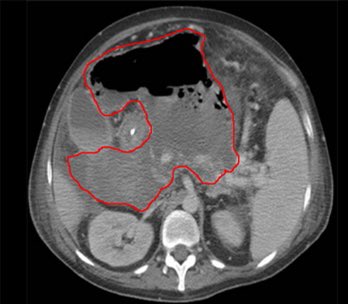

كما لا تقل الاشعة مثل المقطعية اهمية عن باقي الفحوصات في الكشف عن وجود اي مضاعفات للمرض لا سمح الله خصوصا في الحالات التي تحضر لقسم الطواريء. من المضاعفات التي يمكن حدوثها: وجود تجمع صديد داخل البطن (خرّاج)، ثقب في القولون، انسداد في الامعاء، و غيرها مما يستلزم تدخل جراحي.